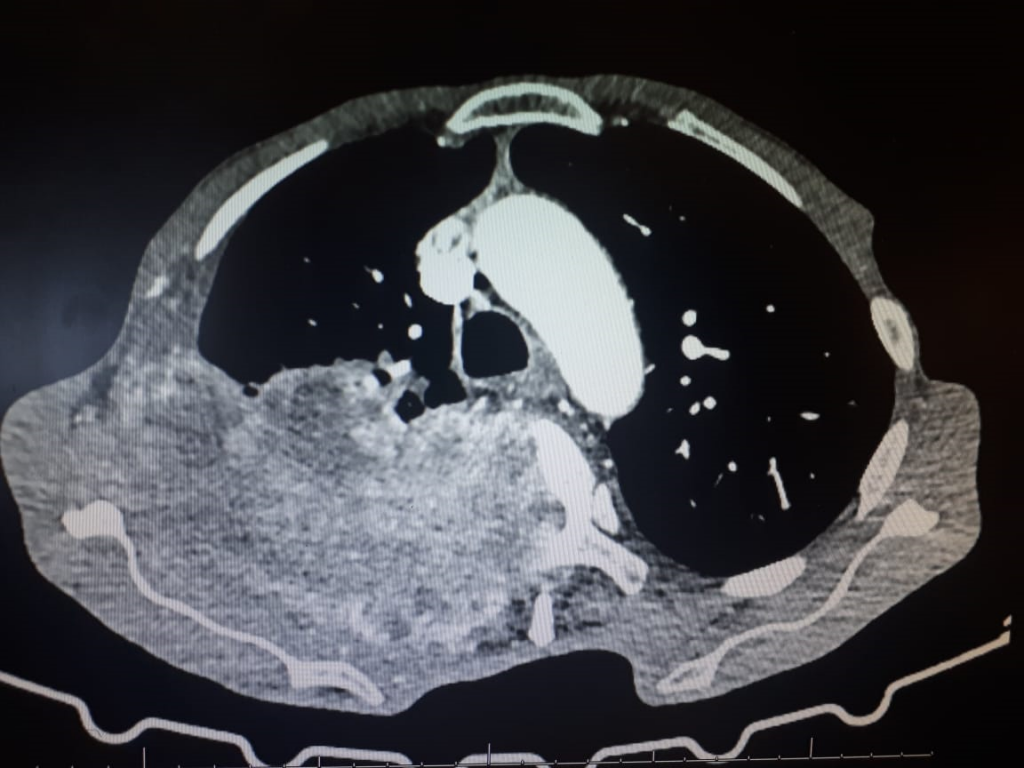

Other Investigations

The patient still had occasional vomiting, abdominal cramps and unexplained muscle pain – other electrolytes apart from calcium, magnesium and phosphate is also advised, as is osmolarity as fluid and electrolyte imbalance may be an effect, rather than a cause of the nausea, vomiting and muscle pain – the sodium and potassium was normal however.

See below, for the hypertension, phaeochromocytoma can be excluded by a 24-hour fractionated urinary metanephrines analysis.

- Primary hyperparathyroidism is on top of the differential diagnosis and is likely the cause of the raised total calcium.

- Another cause of the raised blood pressure could very likely be a phaeochromocytoma.

- Other features of MEN-1 syndrome needs to be excluded.